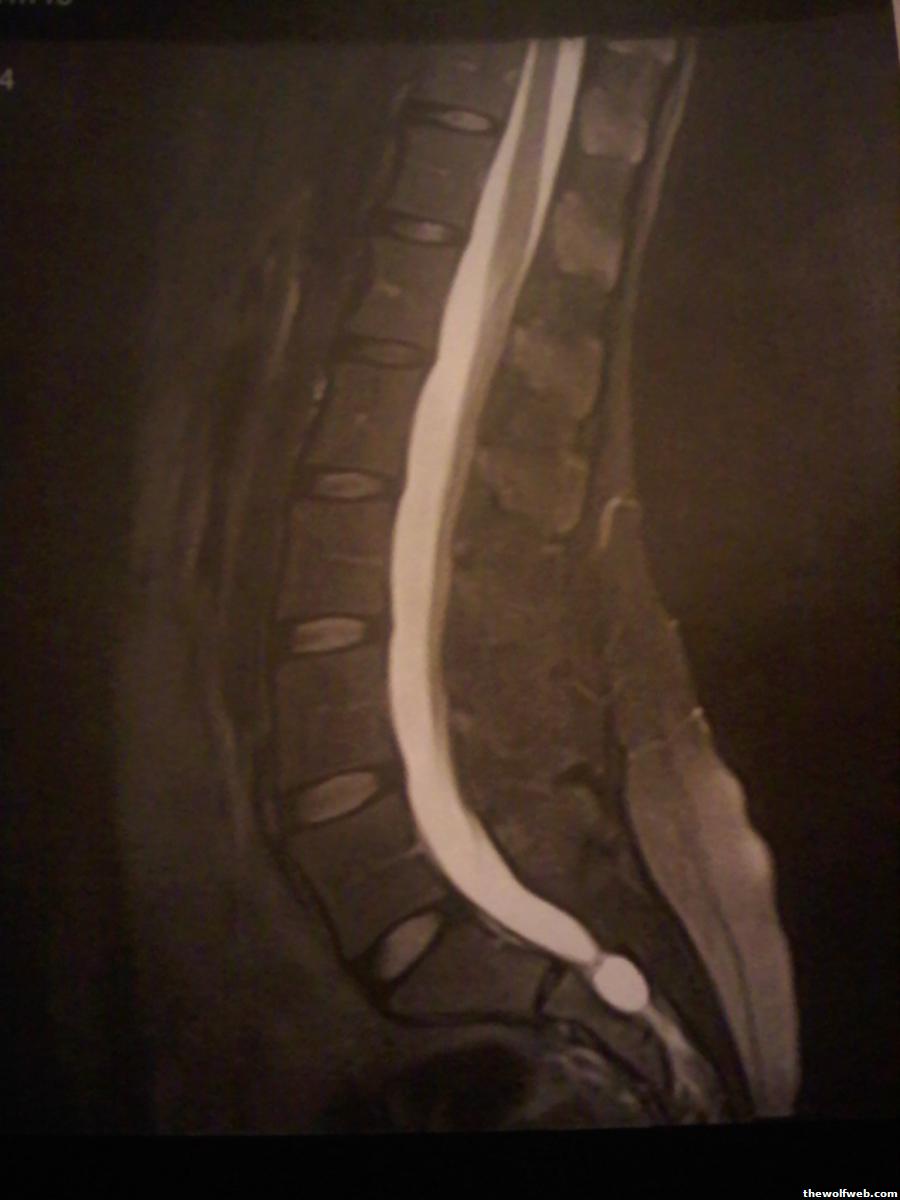

Yep it's a cyst that could POTENTIALLY lead to my paralysis. We're still looking into it.